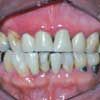

Figure 2

Herpes simplex. The 2 most common infectious conditions in the general practice setting are herpes simplex virus (HSV) infection (type 1 and, less frequently, type 2) (Figure 1) and fungal disease. These conditions are not generally mistaken for each other because their clinical presentations are quite distinct.HSV infection is sometimes confused with aphthous stomatitis (a noninfectious, immunologic-mediated condition precipitated by stress, food sensitivities, trauma, and endocrine disorders) because both of these conditions are characterized by multiple oral ulcerations. However, patients with primary HSV infection--unlike those with aphthous stomatitis (Figure 2)--present with extraoral symptoms including irritability, malaise, headache, and low-grade fever. Further, multiple pinhead lesions are observed on the attached gingiva surrounding the teeth and on the palate, 2 areas not affected in aphthous stomatitis. Both conditions are painful, but pain is generally more severe in patients with herpes simplex. Patients may not be adequately hydrated because drinking is painful. Examination reveals distinct halitosis and submandibular lymphadenitis.1 Both HSV infection and aphthous stomatitis are self-limited, but HSV infection has been associated with morbidity and, in rare cases, mortality.2